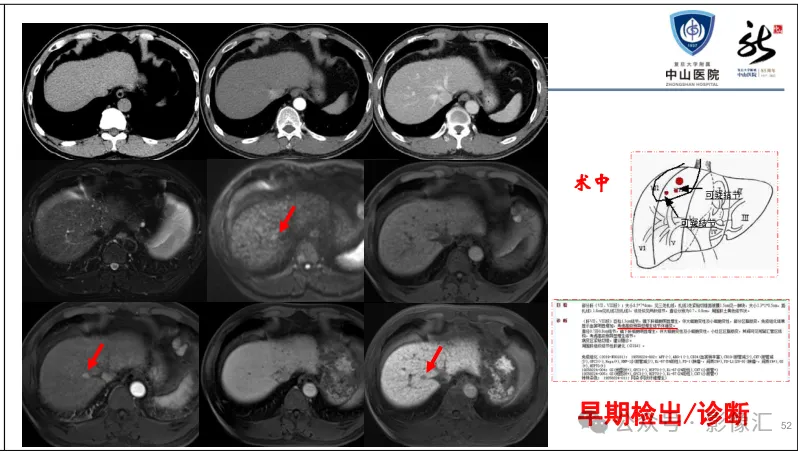

肝胆特异性对比剂增强肝胆图像判读方法与策略,课件来源于网络,作者复旦大学附属中山医院放射科饶圣祥教授。